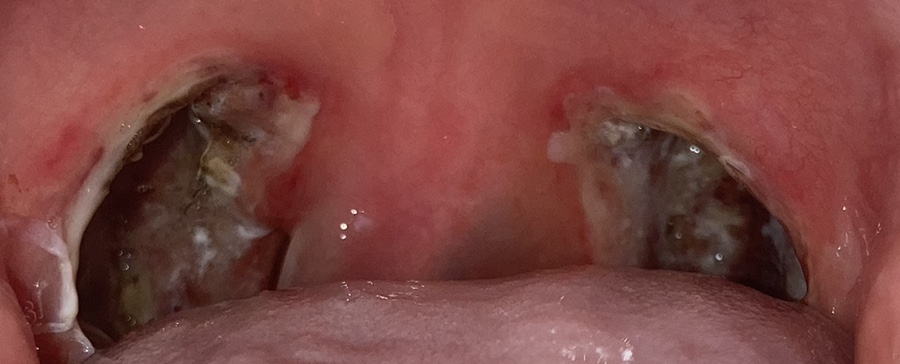

이건 수술 후 사진을 찍은 거야.

딱지가 찔끔찔끔 떨어졌다. 일주일 지나서 괜찮을 것 같아서 한강에 갔는데 약 먹을 시간이 지났을 때 아파서 죽는 줄 알았다.

점점 벗겨지는 게 보여. 그래도 여전히 아프다. 아플 때만 먹으라는 약 하루에 세 번은 꼭 먹게 됐다. 먹지 않으면 아픔을 참을 수 없어.아플 때만 먹으라는 약이 앞면에는 T/A, 뒷면에는 JANSSEN이라고 적혀 있는데 인터넷에서 검색해보면 이름은 울트라셋 정으로 중등도-중증의 급, 만성통증 때 먹는 약이다. 부작용이 과다 복용하면 속쓰림이었는데 제가 이것도 모르고 4개 먹고 토할 것 같아 힘들었던 적이 두 번 있었다. 두 번째가 되고 나서 벌써 세 개 이상은 먹지 않았다.